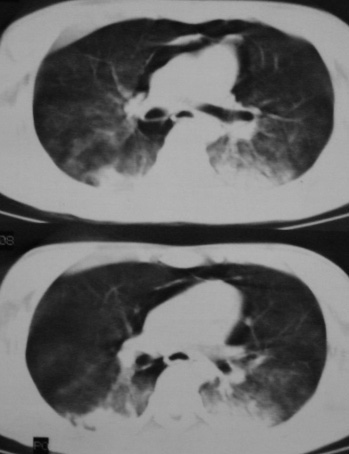

男,18岁,车祸20小时后胸ct.血氧饱和度80,呼吸45次/分.

1:两侧创伤性湿肺(撕裂伤)。

2:纵隔气肿.

支持---1.双肺挫伤,2.纵隔积气。注意右侧主支气管是否有断裂?